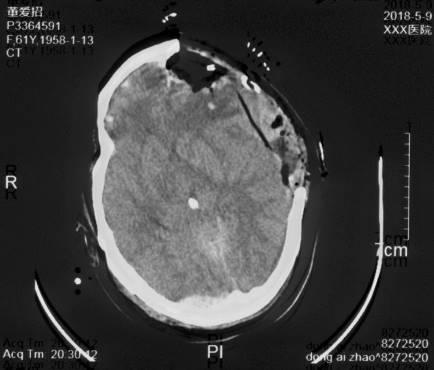

复阅2020年4月29日CT片:左侧额颞部颅骨修补、脑积水分流术后改变,人工颅板在位,双侧额颞叶、左侧枕叶及右侧小脑半球见片状低密度阴影,左侧脑室较右侧稍扩大,内见引流管在位。提示左侧额颞部颅骨修补、脑积水分流术后,双侧额颞叶、左侧枕叶及右侧小脑半球软化灶形成。

图13-15,2020年4月29日 CT片,左侧额颞部颅骨修补、脑积水分流术后,双侧额颞叶、左侧枕叶及右侧小脑半球软化灶形成。